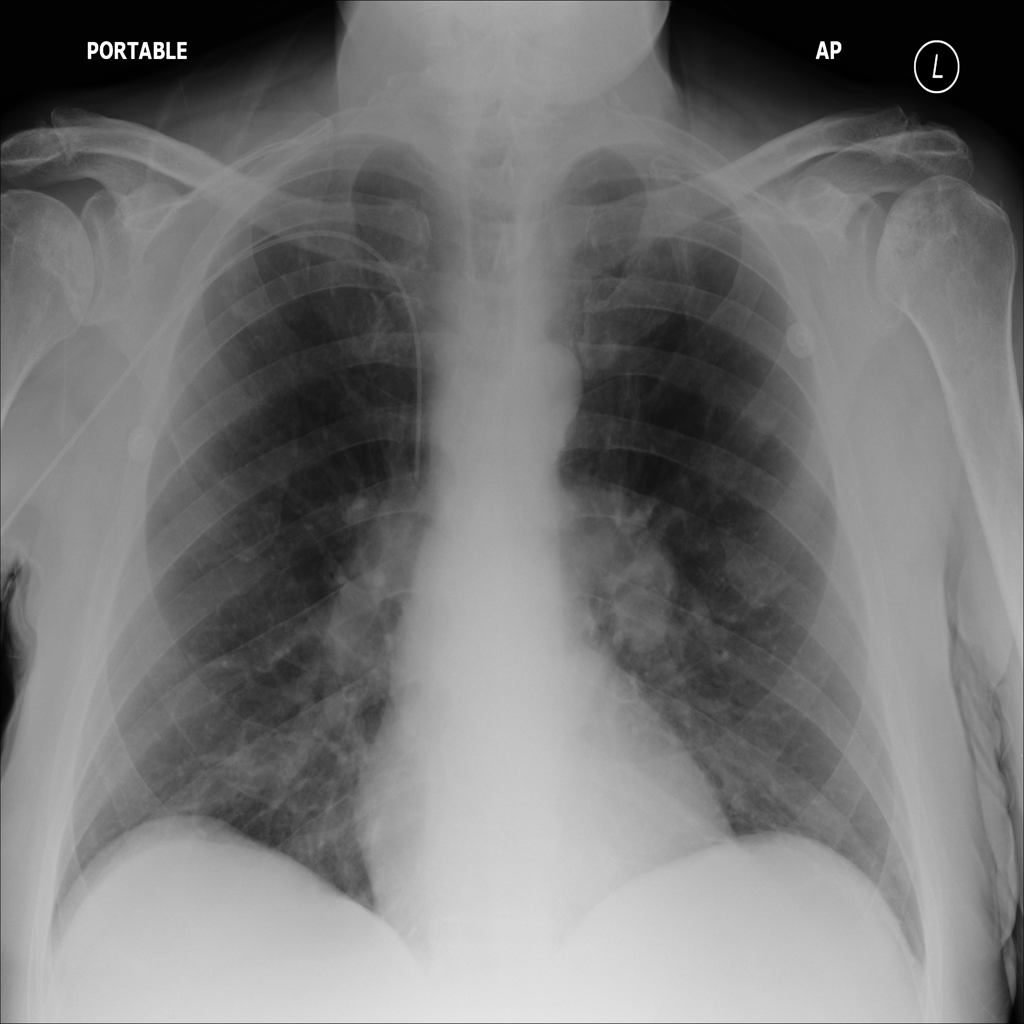

PAT-988D · IMG-001Nodule

PAT-988D · IMG-001

AP